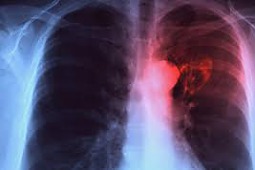

Na łamach czasopisma Thorax ukazała się publikacja, która opisuje wpływ powietrza miejskiego na odpowiedź organizmu na obecność prątków Mycobacterium tuberculosis. U 35 zdrowych, niepalących ochotników z Mexico City zbadano komórki obecne w popłuczynach oskrzelowo-pęcherzykowych i komórki jednojądrzaste krwi obwodowej; pobrany materiał biologiczny (głównie makrofagi) zbadano także pod mikroskopem, poddając wcześniej ekspozycji na PM2,5 w celu oceny wpływu zanieczyszczenia na zdolność do fagocytozy prątków.

Okazało się, że ekspozycja na PM2,5 in vitro nie wpływała istotnie na zdolność do fagocytowania M. tuberculosis. Wykazano, że miejskie zanieczyszczone powietrze powoduje istotny wzrost wytwarzania interleukiny 1β w komórkach obecnych w popłuczynach oskrzelowo-pęcherzykowych oraz wzrost wytwarzania TNFα zarówno w poprzednio wymienionych komórkach, jak i w komórkach jednojądrzastych krwi obwodowej. Ponadto im bardziej nasilone było zanieczyszczenie powietrza tym większa była produkcja interferonu gamma przez makrofagi obecne w pęcherzykach płucnych.

Jak więc widać ekspozycja na miejskie zanieczyszczenie sprzyja rozwojowi przewlekłego stanu zapalnego i w ten sposób może prowadzić do upośledzenia odpowiedzi na prątki gruźlicy. Warto o tym pamiętać szczególnie dlatego, że gruźlica nie jest reliktem minionego wieku - w Polsce rocznie notuje się prawie 6 tysięcy zachorowań i ponad 500 zgonów.